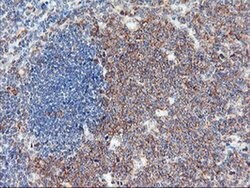

USP10 Mouse anti-Human, Clone: OTI1A10, liquid, TrueMAB™

Ubiquitin is a highly conserved protein that is covalently linked to other proteins to regulate their function and degradation. This gene encodes a member of the ubiquitin-specific protease family of cysteine proteases. The enzyme specifically cleaves ubiquitin from ubiquitin-conjugated protein substrates. The protein is found in the nucleus and cytoplasm. It functions as a co-factor of the DNA-bound androgen receptor complex, and is inhibited by a protein in the Ras-GTPase pathway. The human genome contains several pseudogenes similar to this gene.Specifications

| Flow Cytometry, Immunohistochemistry (Paraffin), Western Blot | |